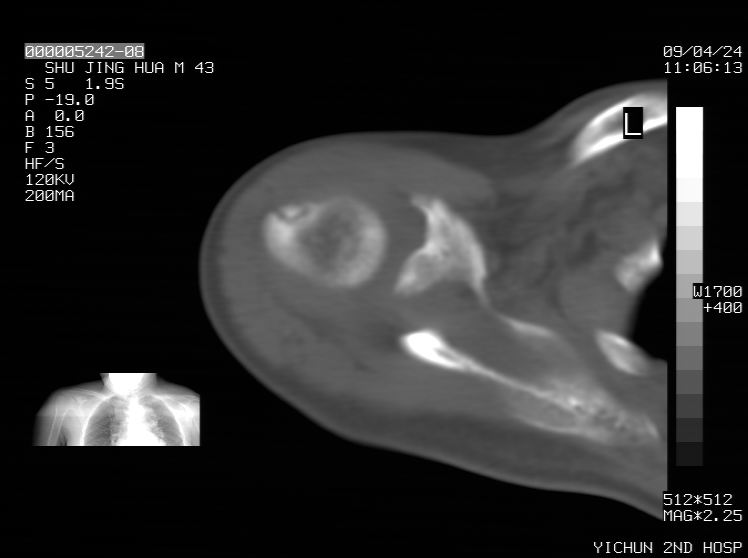

标题: CT19569:请会诊,女50岁,右肩疼痛数月 [打印本页]

标题: CT19569:请会诊,女50岁,右肩疼痛数月

钙化性肌腱炎

是指钙盐沉积在变性肌腱中的一种无菌性炎症,常见于肩关节的肩袖肌腱,引起肩部疼痛和活动受限。分为急性和慢性两种类型,急性型有肩关节突然出现急性疼痛的发作史,夜间可痛醒。